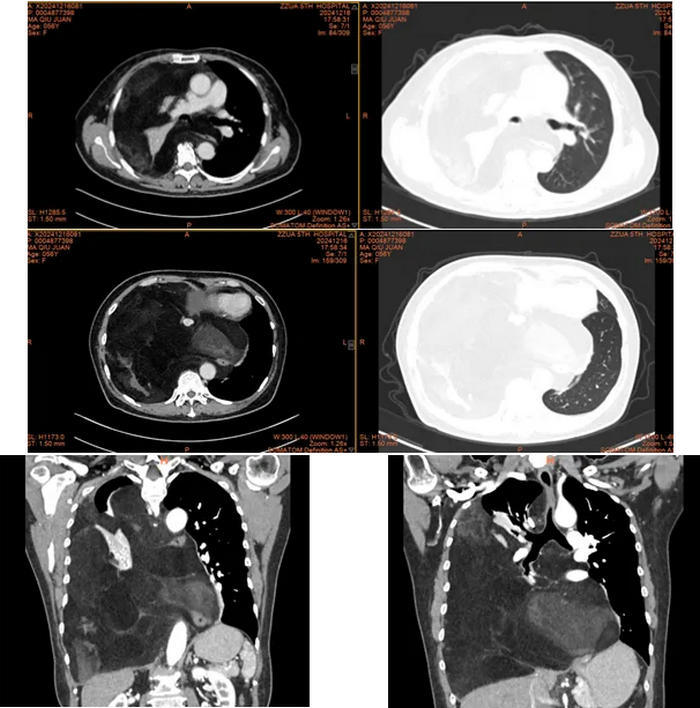

检查发现,马女士右侧胸腔及纵隔内见巨大团片状低密度影,累及左侧胸腔致心脏大血管及气管向左侧胸腔偏移,以脂肪密度为主。肿瘤累及气管、左右主支气管、上腔静脉及主动脉外膜、部分心包、左右下肺静脉,累及并包埋食管及下腔静脉,右肺受压不张。而接下来的手术堪称一场惊心动魄的生命之战。

经过胸外科高兴才主任团队、麻醉科胡强夫主任团队等科室充分准备,输血科魏明主任团队积极备血后,手术按计划如期进行,选择右胸第6肋后外侧切口进胸,因肿瘤体积巨大,占满胸腔,纵隔移位,累及上纵隔、中纵隔、后纵隔,并包绕主动脉及上、下腔静脉、食管。手术空间狭窄,视野受限,术中联合胸腔镜辅助手术,行胸腔及纵隔巨大肿瘤满意切除、心包部分切除。